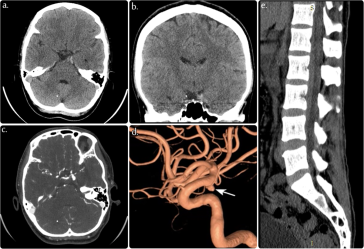

Fatal Ruptured Posterior Communicating Artery Aneurysm A Stark Reminder of Medical Vulnerability

An Opinion on the Digital Safety of Online Healthcare Journals In today’s interconnected world, the assurance of safe and secure access to online healthcare content stands as a critical concern. As we work through tangled issues surrounding patient privacy and data integrity, the digital front lines where healthcare information is communicated and stored have never […] More